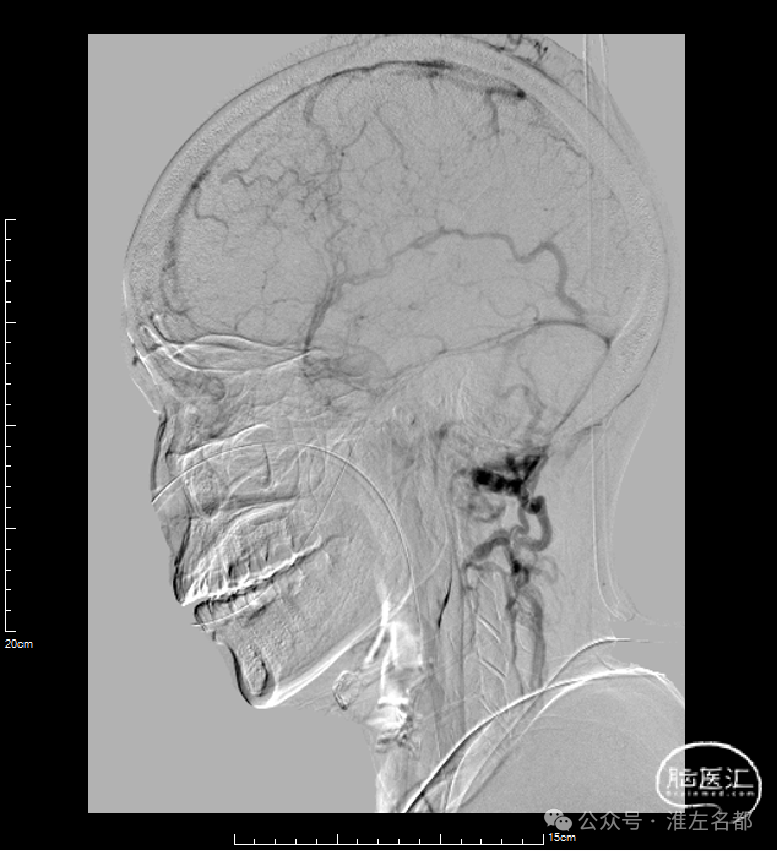

微导丝微导管再次超选直窦,造影示直窦近段狭窄。

3*30mm球囊再次扩张直窦近段,辅以球囊滑动技术。

球囊扩张直窦后造影:直窦近段仍见狭窄。

微导管造影示:右侧横窦-乙状窦仍见明显狭窄。

直窦再次微导管造影:直窦血液引流可。

6*30mm球囊扩张右侧横窦-乙状窦和颅底位置颈内静脉,辅以球囊滑动技术。

介入治疗后右侧颈动脉造影:上矢状窦、直窦和右侧横窦-乙状窦均见显影,右侧横窦局部狭窄明显。